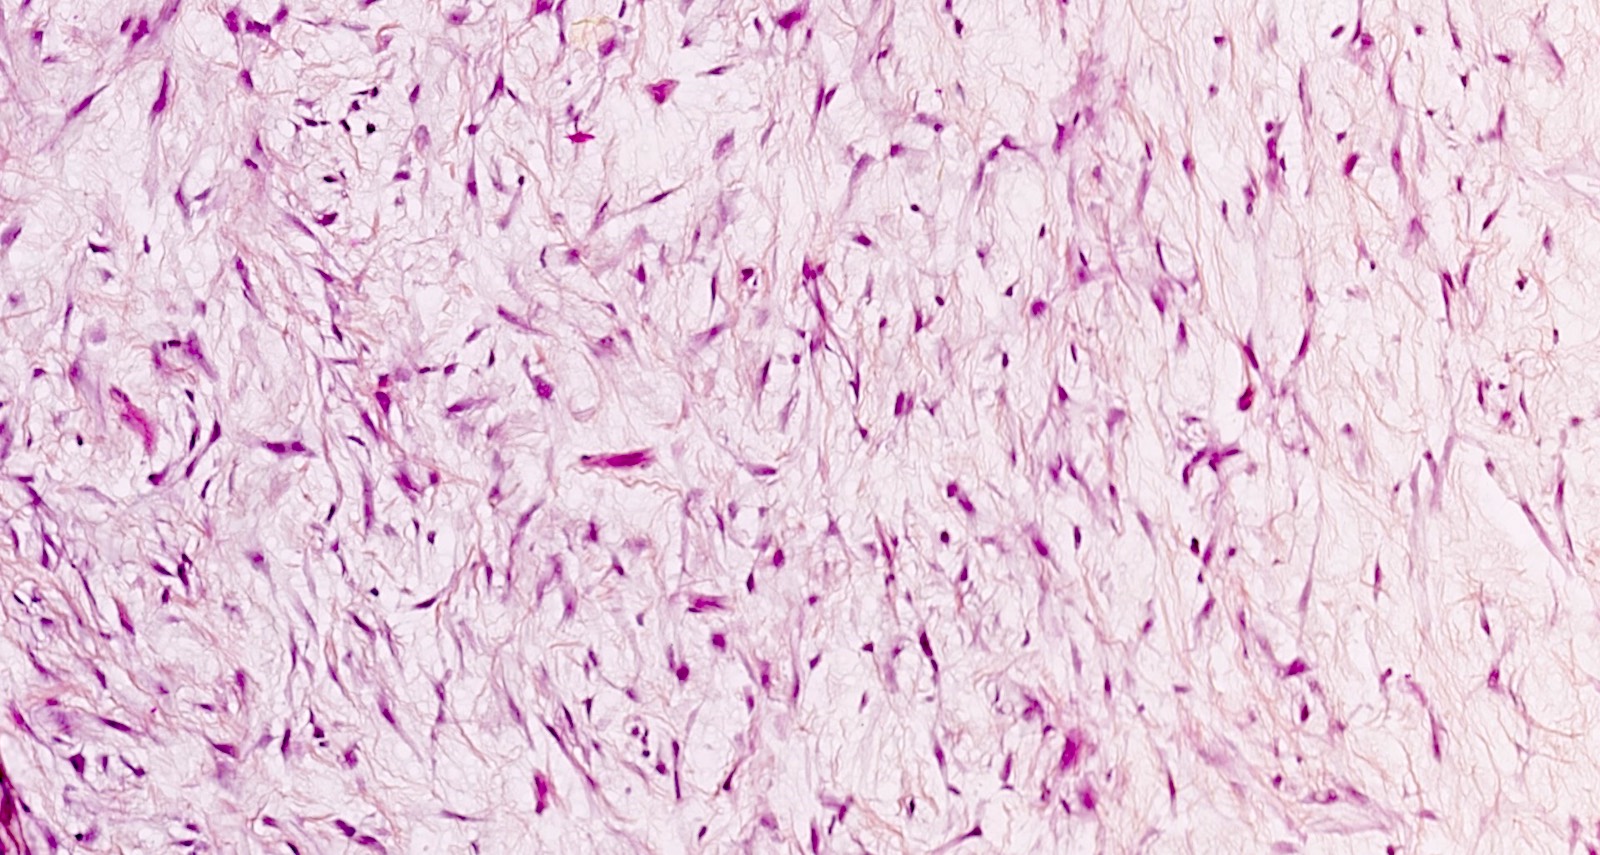

Microscopic (histologic) description

- Conventional / usual leiomyoma (spindle):

- Well defined borders

- Normocellular

- Intersecting fascicles of monotonous spindle cells with indistinct borders, eosinophilic cytoplasm, cigar shaped nuclei (with tapered ends) and small nucleoli

- Atypia: absent or mild

- Mitoses: rare (in general < 5/10 high power fields)

- Blood vessels with thick walls

- With or without infarct type necrosis, hyalinization, calcification, cystic change

Contributed by Sabrina Croce, M.D., Ph.D., Kristina Doytcheva, M.D., Jennifer A. Bennett, M.D. (Case #508) and @Andrew_Fltv on Twitter